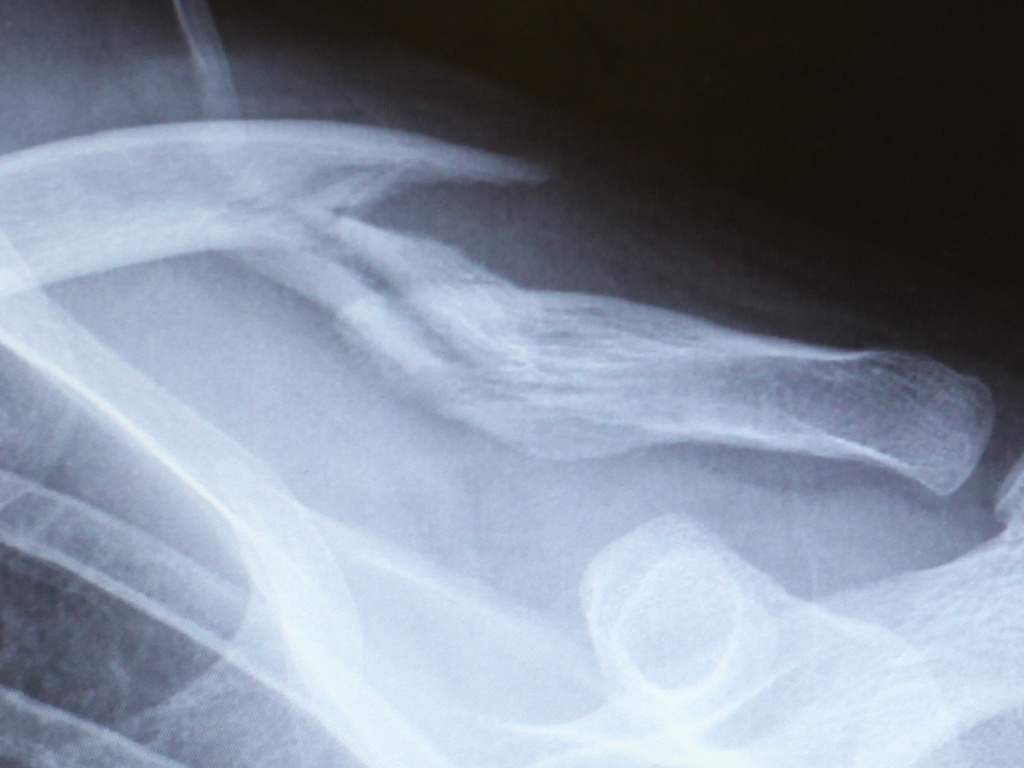

Here are some photos I snapped of the x-rays taken at the Ottawa General Hospital, at various points after my cycling accident:

May 30th – a couple of hours after the accident

[Update: 9 July 2010] Here is an x-ray from today, showing a bit more of the affected area. The biggest difference from the T+19 shot is the round area of bone forming underneath the fracture area. The doctor told me another should form later underneath that sharp protrusion:

T+40 days

What’s it supposed to look like? It doesn’t exactly seem to look… connected.

The emergency room doctors told me that I would be ‘permanently deformed.’ Thankfully, that just means a bit of a bump and some asymmetry.

It is apparently healing essentially as it should be. I hope that spike-shaped protrusion on the upper bone fragment goes away eventually.

That sharp part looks like it could be a future health risk. If you get hit in a certain way, it could be driven forward into your shoulder. Or it could break off and become a pointy disconnected fragment.